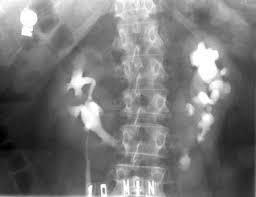

Renal Calculi Solid masses, consisting of collections of tiny crystals that contain calcium Tiny crystals can pass through urine but sometimes they clump and cling to tissue of the kidney, then continue to grow as new crystals are added then harden Commonly seen in renal pelvis Symptoms: hematuria, severe flank pain radiating to groin or genitals Different types: calcium, uric, struvite, staghorn, nephrocalcinosis, and bladder Calcium-most common Uric-associated with gout, radiolucent, seen as filling defect on x-ray Struvite- composed of magnesium ammonium phosphate AKA "infection stones" Common in females Found with UTI's Staghorn Calculus Occurs when a stone begins formation in renal pelvis and continues to grow there, may take that shape Appears as horns on a deer head, blocking the flow of urine